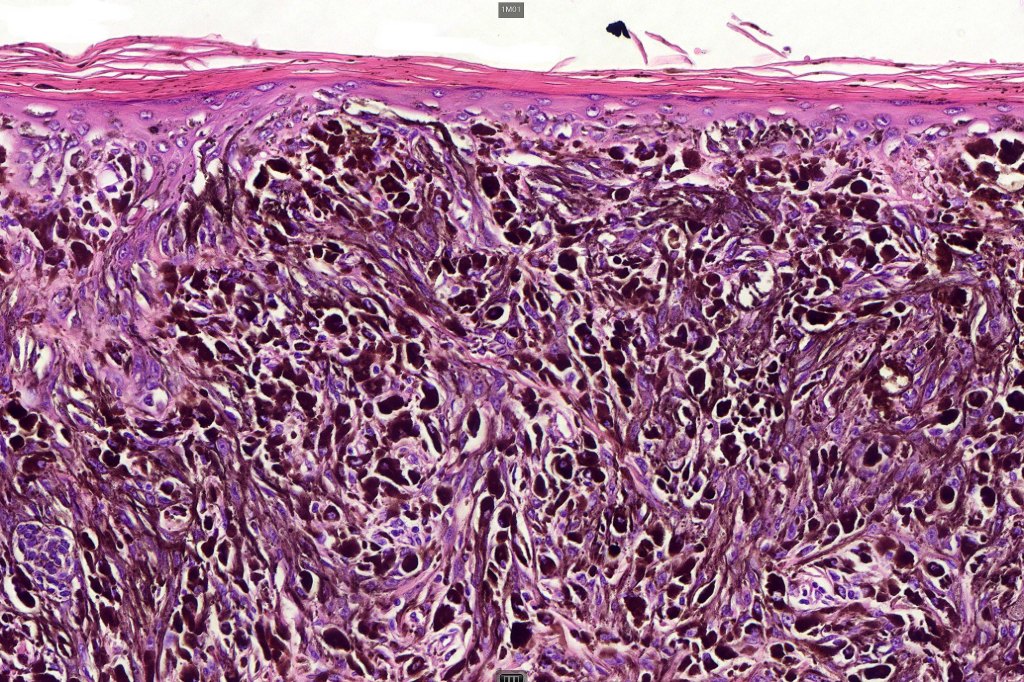

•Dermal of less often compound

•Wedge shape or less often plaque like silhouette

•Commonly associated with marked acanthosis/pseudoepitheliomatous hyperplasia although much less commonly, the epidermis is strteched over the lesion

•Composed of an admixture of large epithelioid melanocytes with vesicular nuclei containing a very prominent nucleolus (fried egg cells), spindle cells, dendritic cells & melanophages

•The epithelioid cells are typically very uniform

•Few mitoses